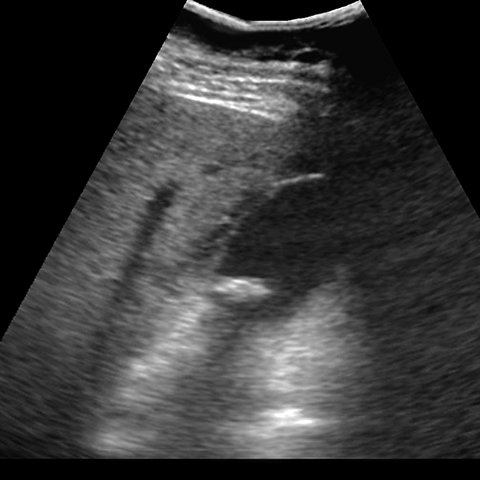

40-year-old obese female presents with colicky right upper quadrant pain [2 of 2]